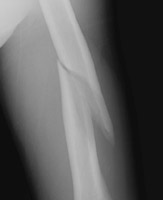

- Click on the image for a larger versionALateral radiograph of the humerus. There is a comminuted fracture of the shaft. Examining the image closely shows a permeative destructive process as well. This patient had lung cancer with other osseous metastases. This is a pathologic fracture.